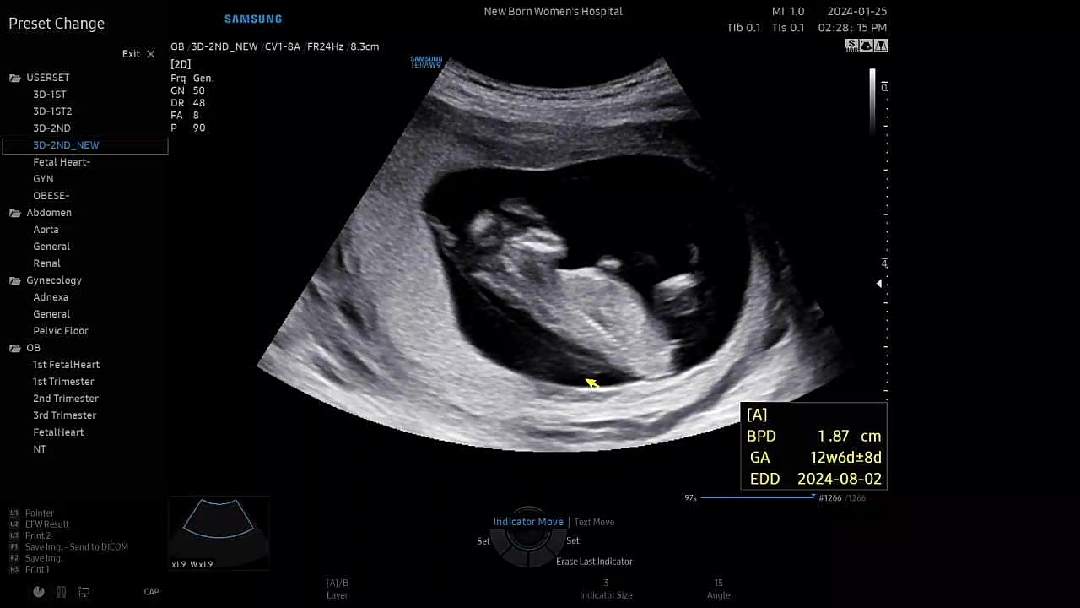

아들같아보이는 초음파사진...성별 뭘까용

요사진은 또아들같기도하구...

그쵸?! 3주뒤에 16주되서 알수있는데 바로아래 초음파사진은 또딸같아서 헷갈리더라구요ㅎㅎ